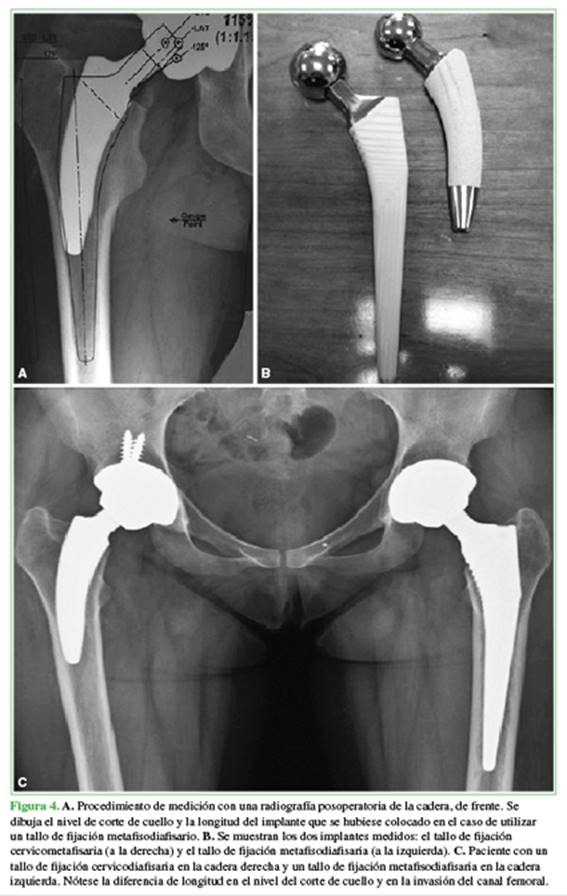

Se llevó a cabo un estudio retrospectivo comparativo en el que se analizaron los primeros 50 vástagos cortos (MiniHipTM, Corin, Cirencester, Reino Unido) con el objetivo de determinar radiográficamente la preservación de capital óseo femoral cuando se había utilizado un vástago corto de fijación cervicometafisaria.27 Fueron analizados con radiografías de frente, midiendo el nivel de resección cervical y la longitud del vástago. Estos fueron comparados con las filminas de un vástago convencional de fijación metafisodiafisaria (MetaFixTM, Corin, Cirencester, Reino Unido).

La programación preoperatoria de los vástagos cortos se realizó según el método descrito por Salvati y cols.,28 y estuvo a cargo de un cirujano con más de 10 años de experiencia en el empleo de este método. Las radiografías posoperatorias digitales de los pacientes en los cuales se implantó un vástago de fijación cervicometafisaria fueron analizadas por dos observadores independientes, superponiendo las filminas de un vástago de fijación metafiso-diafisaria con recubrimiento de hidroxiapatita (MetaFixTM). Se dibujó la longitud del vástago convencional y el nivel de corte del cuello femoral necesario para implantar este tallo. A continuación, se cuantificó la diferencia de preservación ósea longitudinal entre ambos implantes a nivel del cuello femoral y a nivel diafisario, el total como resultado de la suma de ambas mediciones y las longitudes de cada implante (Figura 4A y B).

Los vástagos cortos de fijación cervicometafisaria preservaron radiográficamente, en promedio, 77 mm al compararlos con aquellos de longitud convencional. El corte de cuello en los vástagos convencionales fue entre 3 y 15 mm más distal que con los vástagos cortos (promedio 10 mm). Los implantes convencionales ocuparon 66 mm más de diáfisis (rango 41-81) que los vástagos cortos (p <0,001). La longitud promedio de los vástagos cortos implantados fue de 82 mm (rango 68-102). La longitud promedio de los vástagos convencionales de fijación metafisodiafisaria fue de 142 mm (rango 132-151) (p <0,001) (Tabla 1). De acuerdo con estos resultados, los vástagos cortos permitieron preservar radiográficamente un 42% de longitud ósea comparados con los vástagos de fijación metafisodiafisaria (Figura 4C).